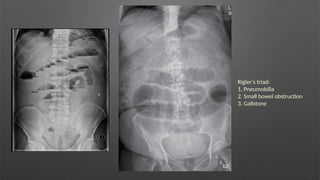

Rigler’s triad:

1. Pneumobilia

2. Small bowel obstruction

3. Gallstone

Rigler’s triad: 1. Pneumobilia 2.Small bowel obstruction 3. Gallstone